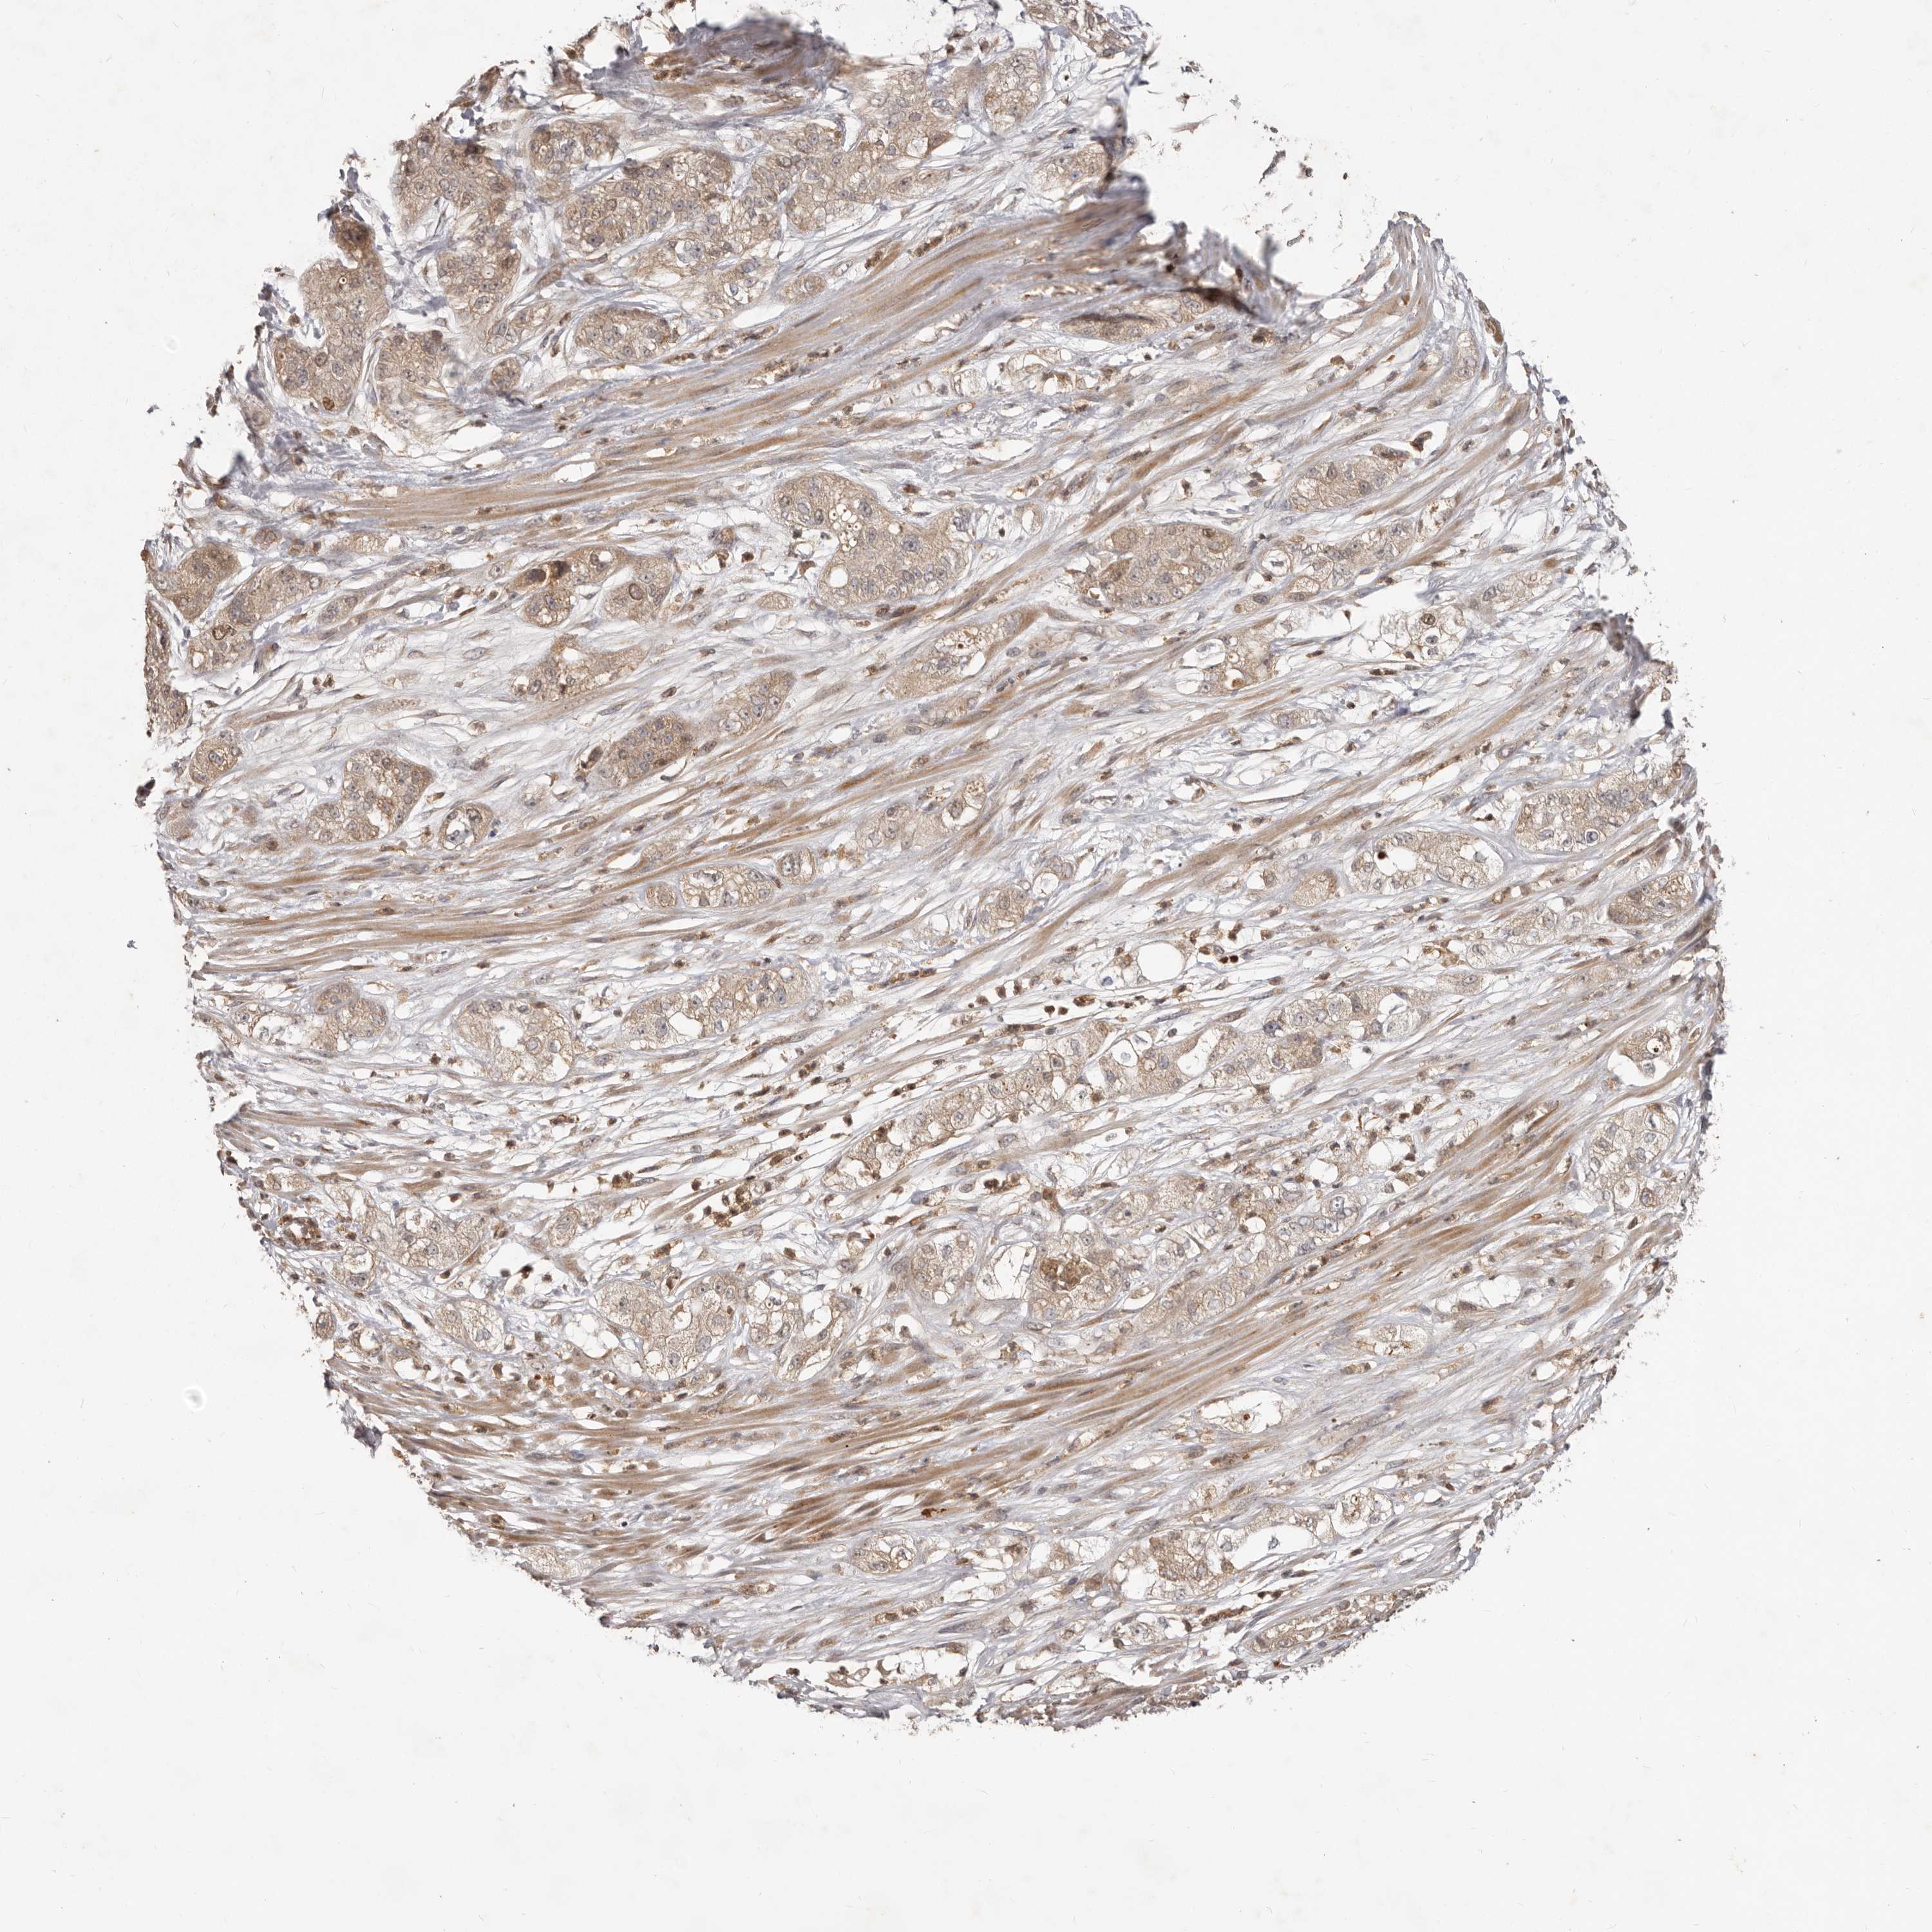

PANCREATIC CANCER - Protein expressioni

A mouse-over function shows sample information and annotation data. Click on an image to view it in a full screen mode. Samples can be filtered based on level of antibody staining by selecting one or several of the following categories: high, medium, low and not detected. The assay and annotation is described here.

Note that samples used for immunohistochemistry by the Human Protein Atlas do not correspond to samples in the TCGA dataset.

Antibody stainingi

Antibody staining in the annotated cell types in the current human tissue is reported as not detected, low, medium, or high, based on conventional immunohistochemistry profiling in selected tissues. This score is based on the combination of the staining intensity and fraction of stained cells.

Each image is clickable and will lead to virtual microscopy that enables deeper exploration of all samples and also displays staining intensity scores, fraction scores and subcellular localization as well as patient and tissue information for each sample.

Antibody HPA030098

Staining

High

Medium

Low

Not detected

Intensity

Strong

Moderate

Weak

Negative

Quantity

>75%

75%-25%

<25%

None

Location

Nuclear

Cytoplasmic/membranous

Cytoplasmic/membranous,nuclear

Adenocarcinoma, NOS